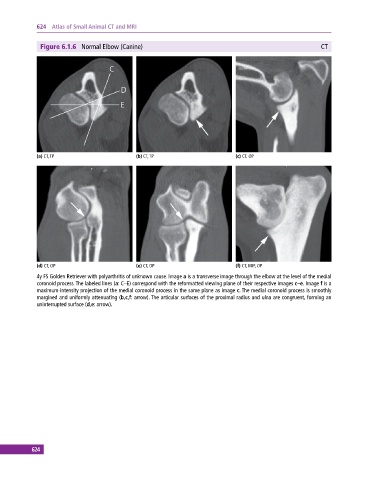

Figure 6.1.6 Normal Elbow (Canine) CT

(a) CT, TP (b) CT, TP (c) CT, OP

(d) CT, OP (e) CT, DP (f) CT, MIP, OP

4y FS Golden Retriever with polyarthritis of unknown cause. Image a is a transverse image through the elbow at the level of the medial

coronoid process. The labeled lines (a: C–E) correspond with the reformatted viewing plane of their respective images c–e. Image f is a

maximum‐intensity projection of the medial coronoid process in the same plane as image c. The medial coronoid process is smoothly

margined and uniformly attenuating (b,c,f: arrow). The articular surfaces of the proximal radius and ulna are congruent, forming an

uninterrupted surface (d,e: arrow).